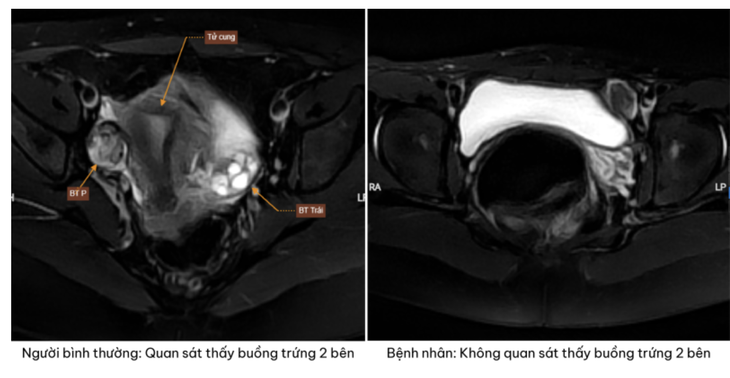

Trên hình ảnh chụp cộng hưởng từ phát hiện bệnh nhân không có tử cung và buồng trứng hai bên - Ảnh: BVCC

Kết quả siêu âm và chụp cộng hưởng từ cho thấy một thực tế khiến cả gia đình bàng hoàng không phát hiện hình ảnh tử cung và buồng trứng ở cả hai bên.

Thay vào đó, tại vùng hạ vị xuất hiện các khối tổ chức nghi ngờ là tinh hoàn lạc chỗ. Đây là dấu hiệu gợi ý đến một rối loạn phát triển giới tính hiếm gặp.